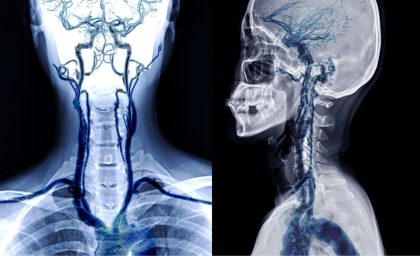

מהי היצרות עורק הקרוטיס? עורקי התרדמה (Carotid Arteries) הם "צינורות החיים" המובילים דם עשיר בחמצן למוח. עם השנים, בדומה לעורקי הלב, גם עורקים אלו עלולים לסבול מהצטברות של רובד טרשתי (פלאק) – שומנים, כולסטרול וסידן. תהליך זה גורם להיצרות העורק ולהפרעה באספקת הדם. למה זה מסוכן? הקשר לשבץ מוחי הסכנה הגדולה ביותר אינה רק החסימה…

המהפכה השקטה: למה חשוב לבדוק את עורקי הצוואר גם כשמרגישים מצוין.

מחקר חדש ב- NEJM ומסר חשוב מפרופ' מיכאל יונש: גילוי מוקדם של היצרות מעל 70% בעורק הקרוטיס – גם ללא תסמינים – וטיפול בצינתור, עשויים למנוע את השבץ הבא. נטיית הלב הטבעית של רובנו היא לגשת לרופא רק כשאנחנו מרגישים כאב או סימפטום חריג. אך כשמדובר בטרשת עורקים ובמניעת שבץ מוחי, ההמתנה לתסמינים עלולה להיות…